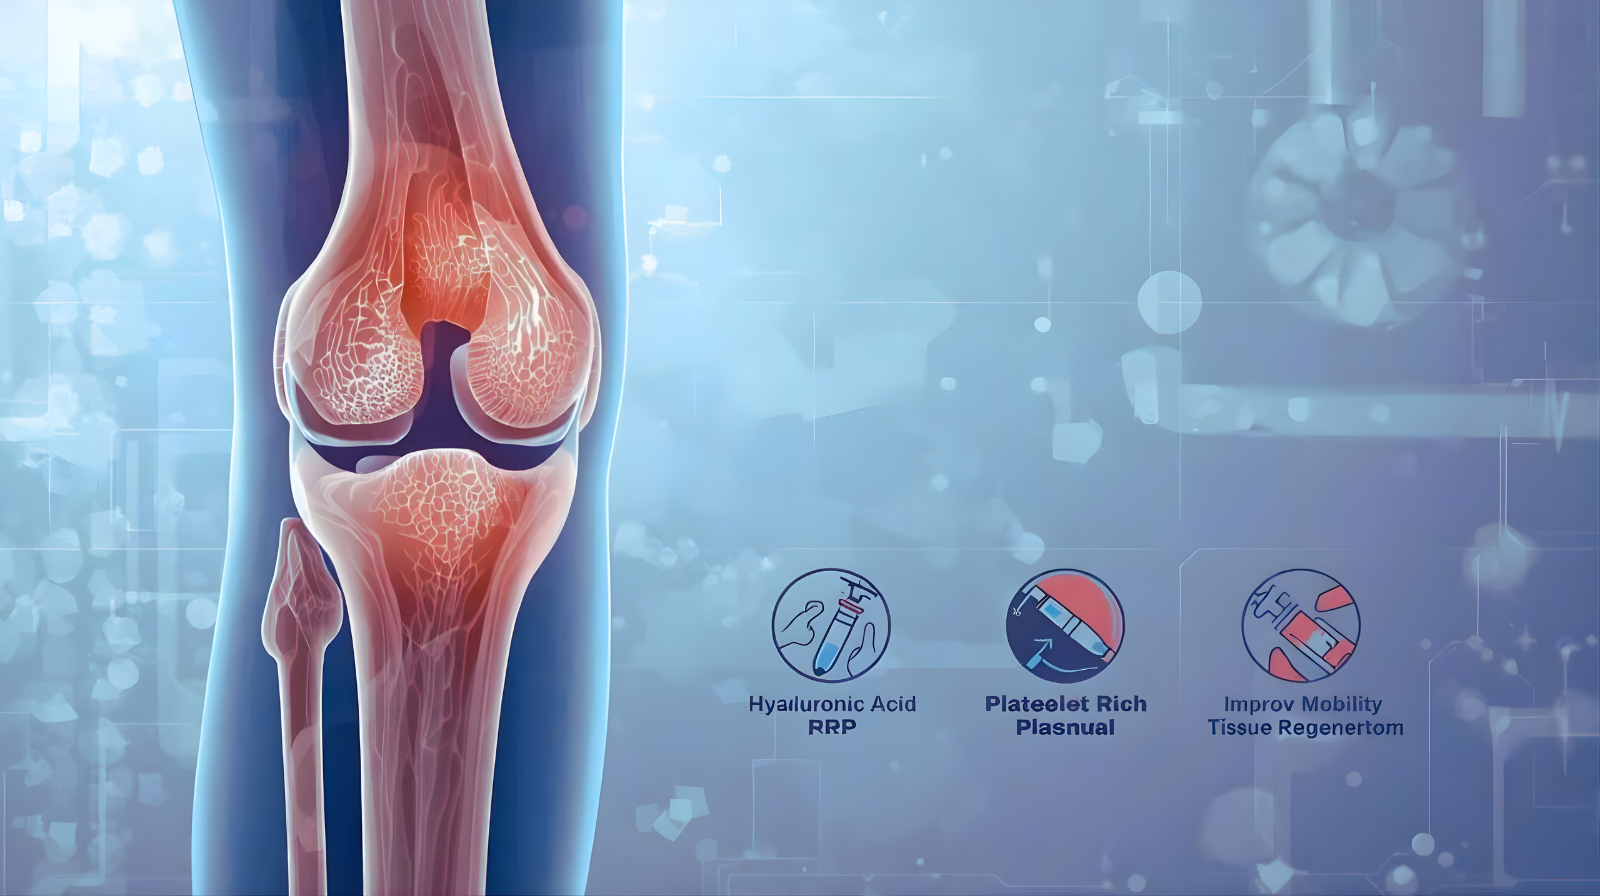

أفضل أنواع حقن خشونة الركبة المعتمدة طبيًا

حقن حمض الهيالورونيك (Hyaluronic Acid):

العمل: يقلد السائل الطبيعي في الركبة، يوفر التزييت ويقلل الاحتكاك.

مناسبة لـ: المراحل المتوسطة، لتحسين الحركة وتخفيف الألم لفترة طويلة.

الاسم الشائع: الحقن الزيتية أو الجيلاتين.

حقن البلازما الغنية بالصفائح (PRP):

العمل: تستخدم عوامل النمو الموجودة في بلازما دم المريض لتحفيز شفاء الأنسجة وتجديدها.

مناسبة لـ: تحفيز عملية الشفاء وتجديد الغضروف.